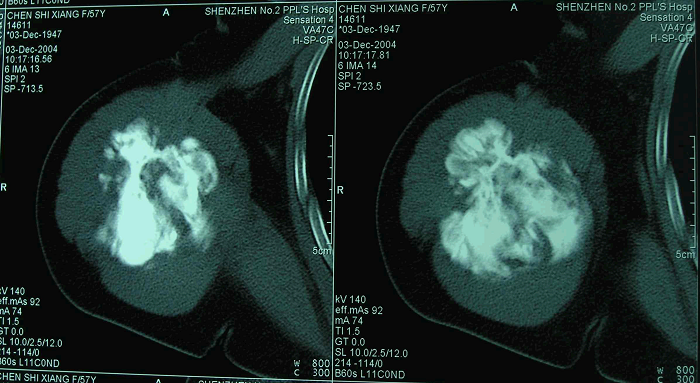

4、病例4:女 58岁 右肱骨中上段髓内高分化骨肉瘤,行瘤段广泛切除异体半关节移植术

图 21 术前CT横断面象

图 22 术前CT冠状面象

图 23 术前CT三维重建象

图 24 术后X线片

图 25 组织学特点:纤维性间质,产生胶元的梭形细胞交织排列,数量不等的骨样基质,成骨细胞有一定异型,肿瘤形成较多层状骨。